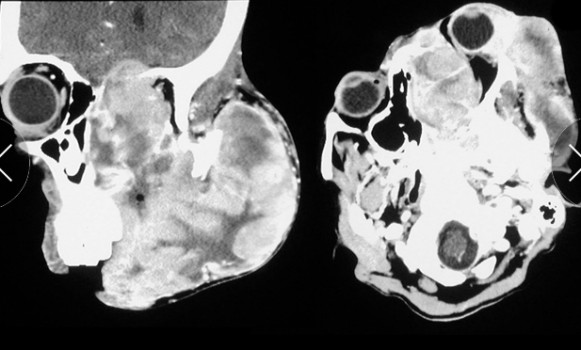

上图是上述病人显示的CT影像。左为矢状扫描,显示患者的左上颌骨广泛破坏以及左侧鼻窦组织的暴露,左眼眶被肿瘤组织占据。右为轴向扫描,显示肿瘤侵袭左侧眼眶,造成上睑下垂,以及肿瘤延伸到左筛窦及颞颞下窝。